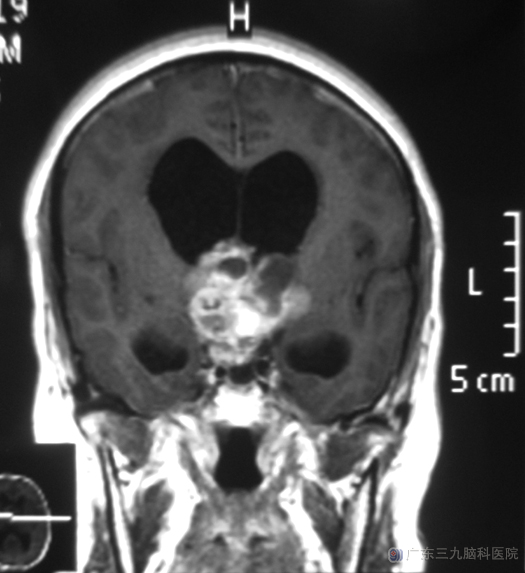

近半个月,培叔觉得有点头痛,视力也开始下降,大哥建议他去医院检查一下。头颅CT检查提示:鞍区占位,考虑颅咽管瘤的可能性大。在广东三九脑科医院进一步检查,头颅MR提示病变大小约5.4cm×4.3cm×4.3cm。

综合神经外科 鲁明主任主刀,在全麻下行经额右侧纵裂入路鞍上三脑室肿瘤切除术,显微镜下见肿瘤位于鞍上,呈灰白色,用双极电凝并肿瘤分块切除,对下丘脑、垂体柄及重要血管保留完整,手术顺利。现已康复出院,术后病理结果:颅咽管瘤。

颅咽管瘤是由外胚叶形成的颅咽管残余的上皮细胞发展起来的一种常见的胚胎残余组织肿瘤,为颅内最常见的先天性肿瘤。颅咽管瘤压迫下丘脑及垂体还可引起多种内分泌代谢紊乱和下丘脑功能障碍,肿瘤破坏视上核或神经垂体,可引起尿崩症,患者每天饮水在3000~4000ml以上。

颅咽管瘤最常见的部位是在鞍区,属于颅脑的中心地带,位置深,并且周围有视神经、颈内动脉、大脑前动脉、垂体、下丘脑等主要结构,常常与下丘脑粘连,手术视野狭小深在,手术难度很大。http://www.999brain.com/